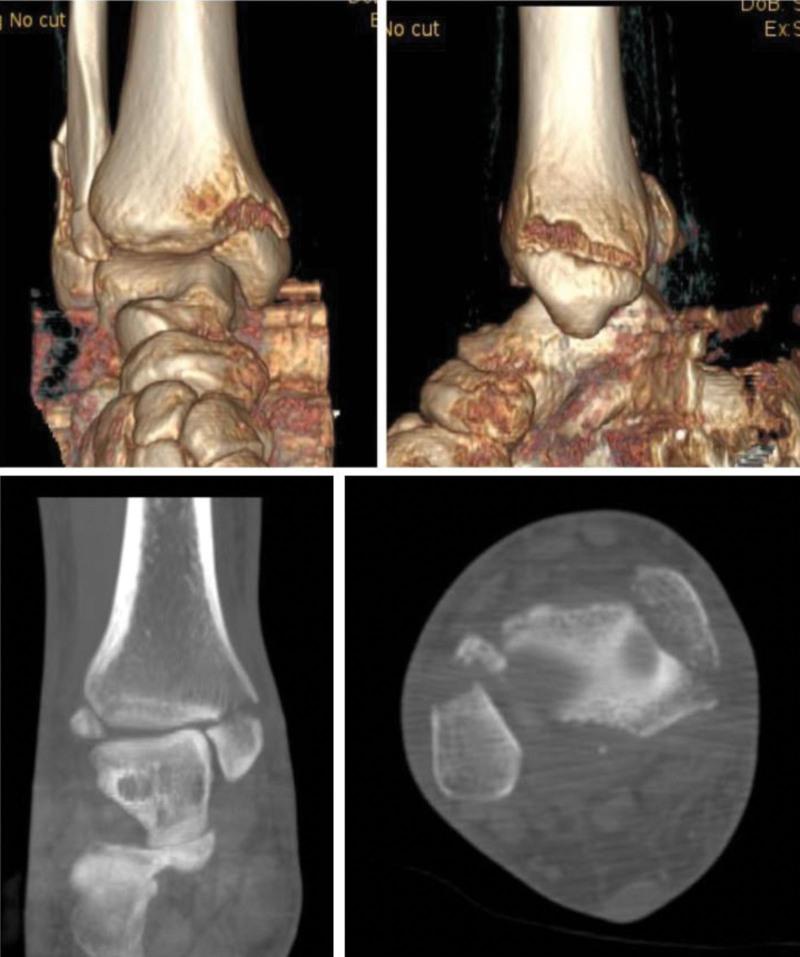

In our study, we report a case of 36 year-old man diagnosed with trimalleolar fracture accompanying ankle dislocation initially. The patient was admitted to our hospital due to traffic accident.

The patient was diagnosed with trimalleolar fracture accompanying ankle dislocation initially. We missed the diagnosis of accompanied deltoid ligament due to the arthralgia of medial ankle and the widened medial articular space in X-ray after operation.